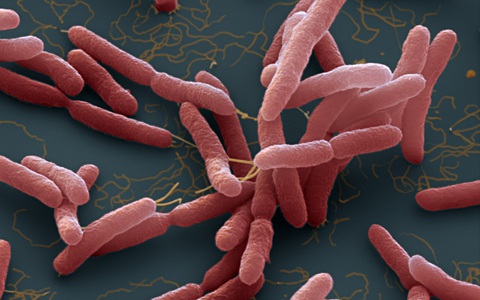

Rất nhiều ca nhiễm và tử vong do "vi khuẩn ăn thịt người" (bệnh Whitmore). Bệnh khó chẩn đoán và nhiều người còn chưa biết đến căn bệnh chết người này để phòng tránh.

CDC đã đưa ra khuyến cáo đối với các cơ sở y tế sau khi lần đầu tiên phát hiện vi khuẩn Burkholderia pseudomallei gây bệnh Whitmore trong mẫu đất và nước ở Mỹ.

TTO - Trường hợp bé gái 9 tuổi ở Đắk Lắk bị nhiễm Whitmore (do vi khuẩn Burkholderia pseudomallei gây ra, còn gọi 'vi khuẩn ăn thịt người') lại dấy lên nỗi lo lắng khi chúng xâm nhập vào cơ thể, gây tổn thương nhiều cơ quan.